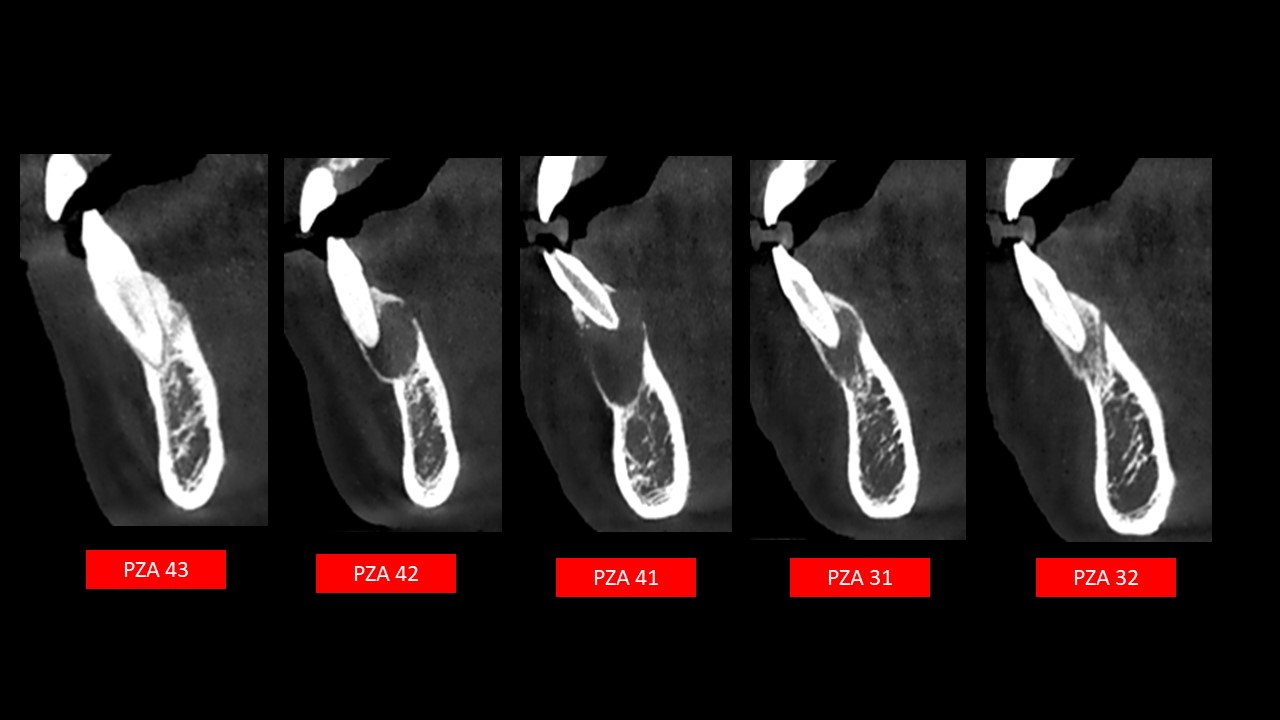

Figura 4

En los cortes coronales(Figura 4) se observa que está localizada entre las piezas 32- 43 y que genera el adelgazamiento de la cima del reborde alveolar junto con la pérdida de lámina dura a nivel del tercio medio radicular medio y apical de piezas 32,31,41 y 42.

Figura 6

Siguiendo el eje de las piezas (Figura 6) , se observa atrición incisal con compromiso pulpar en la pieza 41, evidenciando un aumento del ancho del conducto radicular y una irregularidad a nivel del tercio apical lingual, lo que indicaría que el origen de la lesión estaría asociado a dicha pieza.